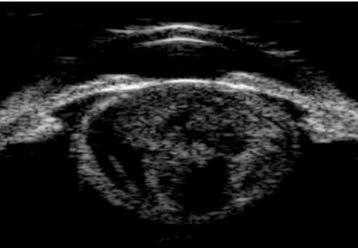

Presentamos el caso de una paciente de 81 años con agudeza visual de ‘cuenta dedos’ en el ojo derecho y antecedente de trabeculectomía, cuya ampolla filtrante superior se encontraba funcional, pero marcadamente adelgazada (Figuras 1 y 2).

A la exploración, destacaba una catarata hipermadura, PIO de 9 mmHg y daño glaucomatoso avanzado (copa/disco 0.9).

La estrategia quirúrgica se definió mediante la microscopia especular y la UBM: un RCE crítico de 997 células/mm² (Figura 3) y un cristalino de gran diámetro anteroposterior con lens vault aumentado (Figura 4).

Figura 4. UBM mostrando catarata con aumento del diámetro AP y del lens vault